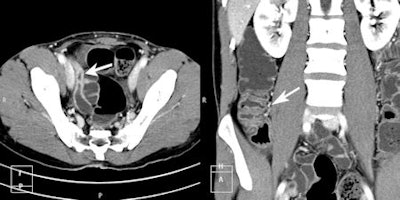

A total of 15 (20.5%) of the 73 patients had positive findings on CTE related to small-bowel pathology, and 12 (16.4%) had nonsmall-bowel pathology that could explain clinical symptoms. Most prevalent small-bowel findings were in the inflammatory bowel subgroups (either known or suspected), where six (30%) patients out of 20 had signs of active inflammatory bowel disease (IBD).

In the group of patients with known IBD, 3 (37.5% of subgroup) had signs of active inflammation and one patient had perianal fistulae. In the group referred with possible IBD, 3 (25% of subgroup) patients had signs of active IBD, one had ileocecal intussusception and one had a small-bowel mass lesion. This proved to be a hamartoma at histology following surgical resection.